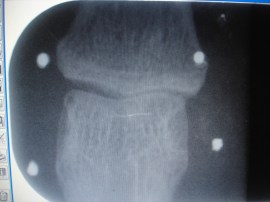

La utilización de los implantes de oro es más frecuente en grandes articulaciones. En este artículo se presenta la colocación de implantes en una artrosis interfalángica proximal del 3º dedo de la mano. La flexión está limitada y la paciente refiere impotencia funcional por dolor que limita su actividad profesional (es ginecóloga). Mediante el examen clínico se observa la tumefacción y engrosamiento digital. En la exploración radiológica se aprecia el pinzamiento articular especialmente en el lado radial de la articulaciòn. Se pueden verlos implantes de oro periarticulares. Debido a las particularidades de la inserción capsular en las articulaciones interfalángicas, los implantes distales se colocan más próximos a la articulación que los implantes colocados a los lados del cuello de la primera falange